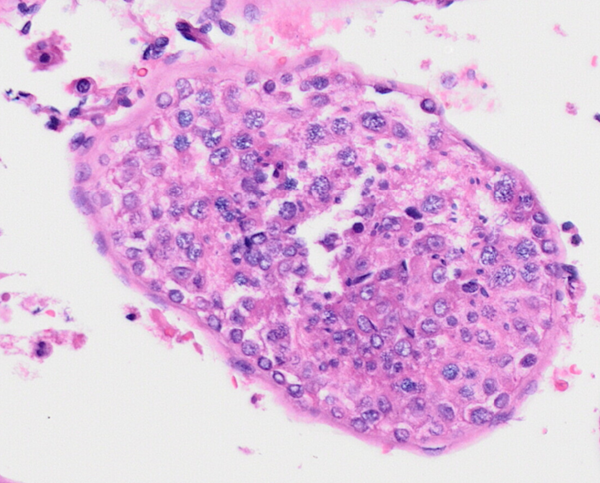

病理医生可以从常规的睾丸病理切片(HE染色)中识别各类生精细胞(如图2),并依据个人经验做出病理诊断。但在实际工作中,单纯依靠人工镜下观察,暴露出主观性强、诊断一致性差、缺少定量分析等弊病。

图2 生精功能正常的睾丸病理分析模式图(上)和显微镜下的图像(下)